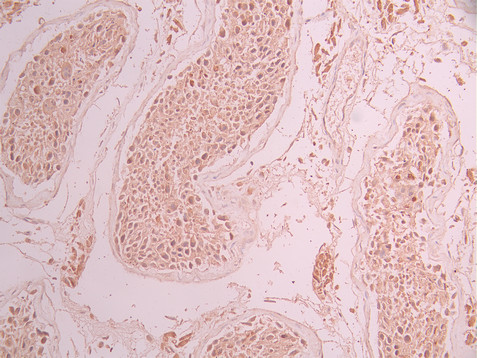

• IHC image of CSB-RA798534A0HU diluted at 1:100 and staining in paraffin-embedded human testis tissue performed on a Leica BondTM system. After dewaxing and hydration, antigen retrieval was mediated by high pressure in a citrate buffer (pH 6.0). Section was blocked with 10% normal goat serum 30min at RT. Then primary antibody (1% BSA) was incubated at 4°C overnight. The primary is detected by a Goat anti-rabbit polymer IgG labeled by HRP and visualized using 0.05% DAB.